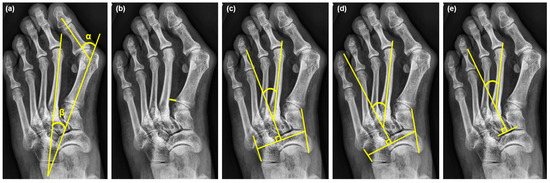

2.2. Radiographic Measurements